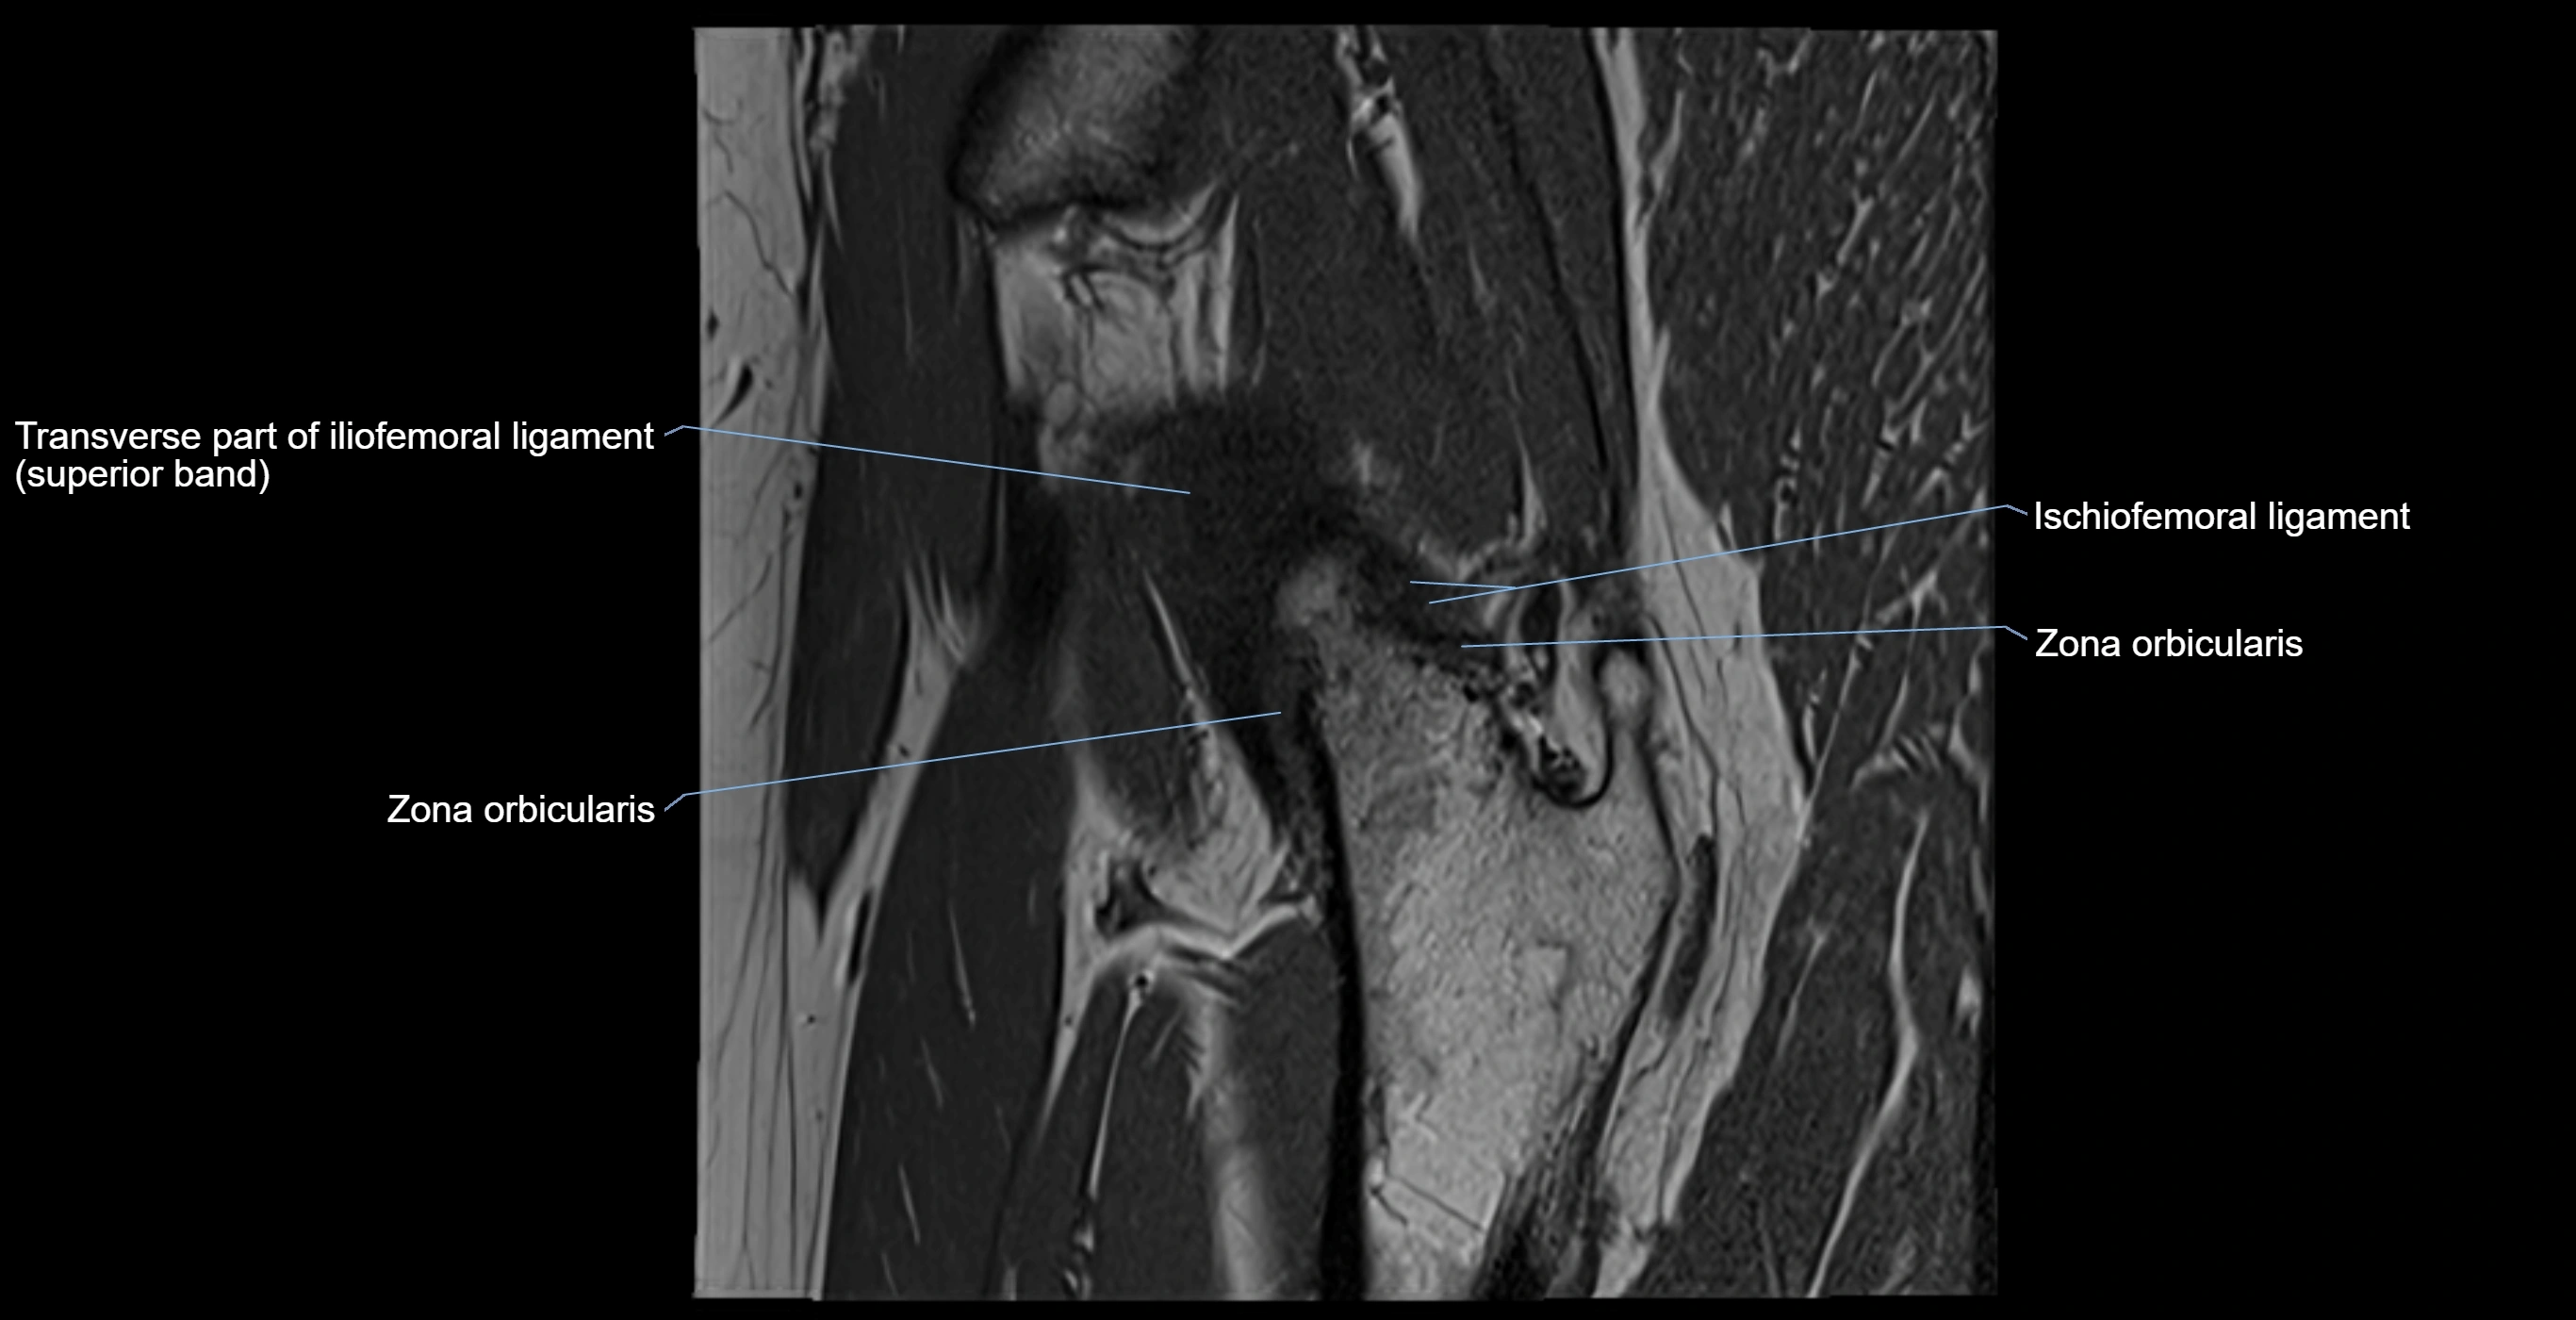

MRI Appearance

T1-weighted images:

• Labrum: low signal intensity (dark)

• Surrounded by intermediate signal joint fluid (bright on arthrogram)

• Tears: linear or focal areas of intermediate-to-high signal interrupting labral continuity

T2-weighted images:

• Joint fluid: bright, making labral tears visible as fluid extending into or around labrum

• Degeneration: may show areas of increased signal within labrum

MRI image

image